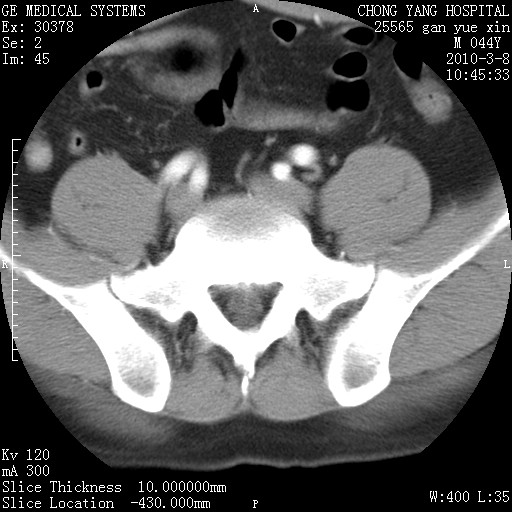

标题: CT24940:主动脉增强,典型病例。 [打印本页]

标题: CT24940:主动脉增强,典型病例。

夹层动脉瘤。

动脉夹层

夹层动脉瘤,典型

主动脉夹层。

动脉夹层的分型:

⒈debakey分型:根据主动脉夹层累及部位,分为三型:ⅰ型:原发破口位于升主动脉或主动脉弓部,夹层累及升主动脉、主动脉弓部、胸主动脉、腹主动脉大部或全部,少数可累及髂动脉。ⅱ型:原发破口位于升主动脉,夹层累及升主动脉,少数可累及部分主动脉弓。ⅲ型:原发破口位于左锁骨下动脉开口远端,根据夹层累及范围又分为ⅲa,ⅲb。ⅲa型:夹层累及胸主动脉。ⅲb型:夹层累及升主动脉、腹主动脉大部或全部。少数可累及髂动脉。

⒉stanford分型:a型:夹层累及升主动脉,无论远端范围如何。b型:夹层累及左锁骨下动脉开口以远的降主动脉。

夹层动脉瘤,少量胸水

夹层动脉瘤;左侧少量胸腔积液。

典型主动脉夹层。